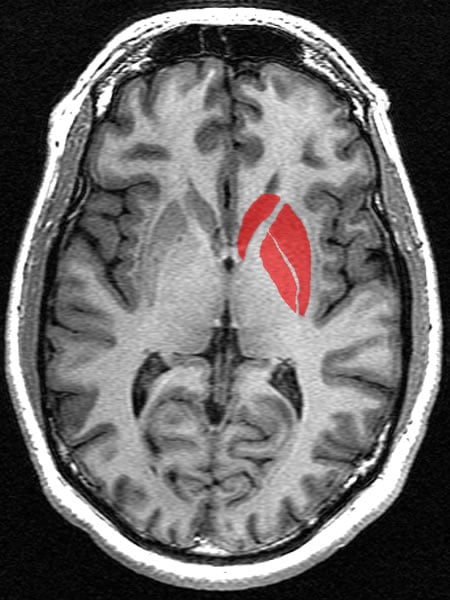

Comparing the two groups, the researchers detected reduced conflict-related functional activity in several cortical areas of the CHR group compared with healthy controls. These areas included the dorsolateral prefrontal cortex or DLPFC (a functional control region of the brain with a long period of maturation leading into adolescence) and the dorsal striatum (involved in reward and decision-making). Higher levels of conflict-related activation in these areas as shown by fMRI were associated with better social and role outcome. Furthermore, the study showed that conflict-related activations in the DLPFC of those CHR individuals who ultimately developed psychosis were smaller than in those who did not.

Image Source: The image is credited to Lindsay Hanford, Geoff B Hall and is in the public domain